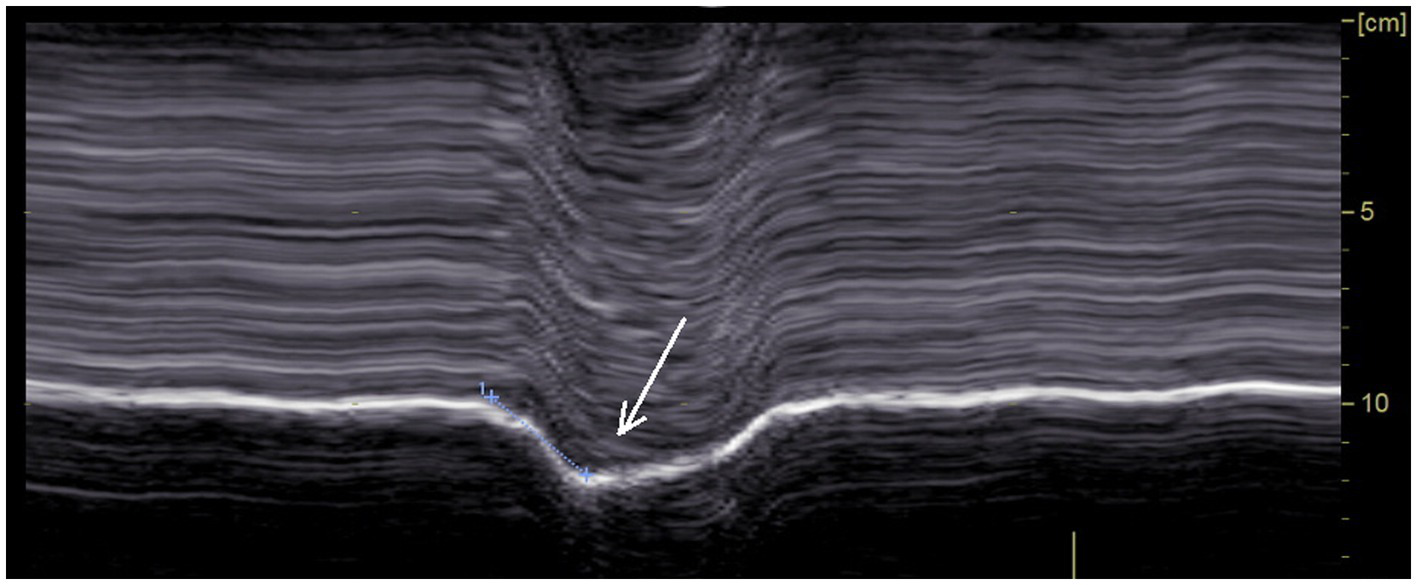

The analysis of diaphragm motion during sniffing, has demonstrated its interest for the diagnosis of hemidiaphragm paralysis when the recording was carried out by fluoroscopy (45) and more recently by ultrasound (24, 25). In our study, as expected, during sniffing a paradoxical motion of paralyzed hemidiaphragm was recorded (Figure 2), plausibly because of the decrease in chest pressure. This movement registered by M-mode ultrasound was a quick paradoxical displacement reaching about −1 cm (from −0.3 to −2.4 cm). In some patients, paradoxical motion was low (<0.5 cm) and no paradoxical motion was found in one case. Sniffing may be difficult to adequately perform for some patients. In addition, it was reported, using fluoroscopy, that some healthy subjects exhibited paradoxical diaphragm movement during sniffing (45). Consequently, recording of the hemidiaphragm excursion during quiet breathing and deep inspiration, may be useful as it supports the diagnosis of paralyzed hemidiaphragm.

Figure 2

Paradoxical motion recorded during voluntary sniffing.